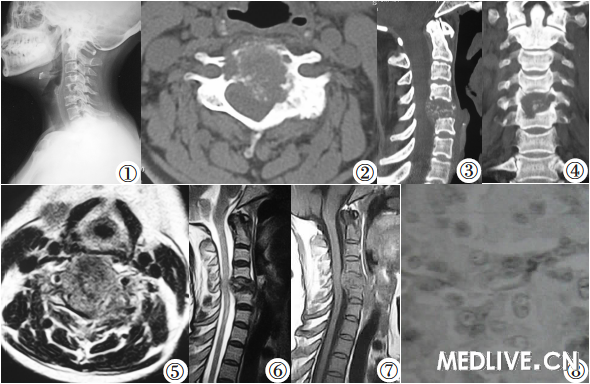

颈椎侵袭性骨母细胞瘤1例

反应性间质,骨小梁周有骨母细胞围绕.